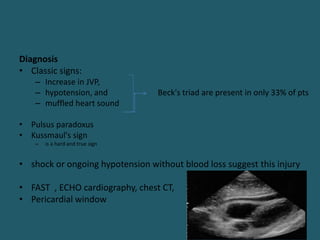

Diagnosis

• Classic signs:

– Increase in JVP,

– hypotension, and Beck's triad are present in only 33% of pts

– muffled heart sound

• Pulsus paradoxus

• Kussmaul's sign

– is a hard and true sign

• shock or ongoing hypotension without blood loss suggest this injury

• FAST , ECHO cardiography, chest CT,

• Pericardial window